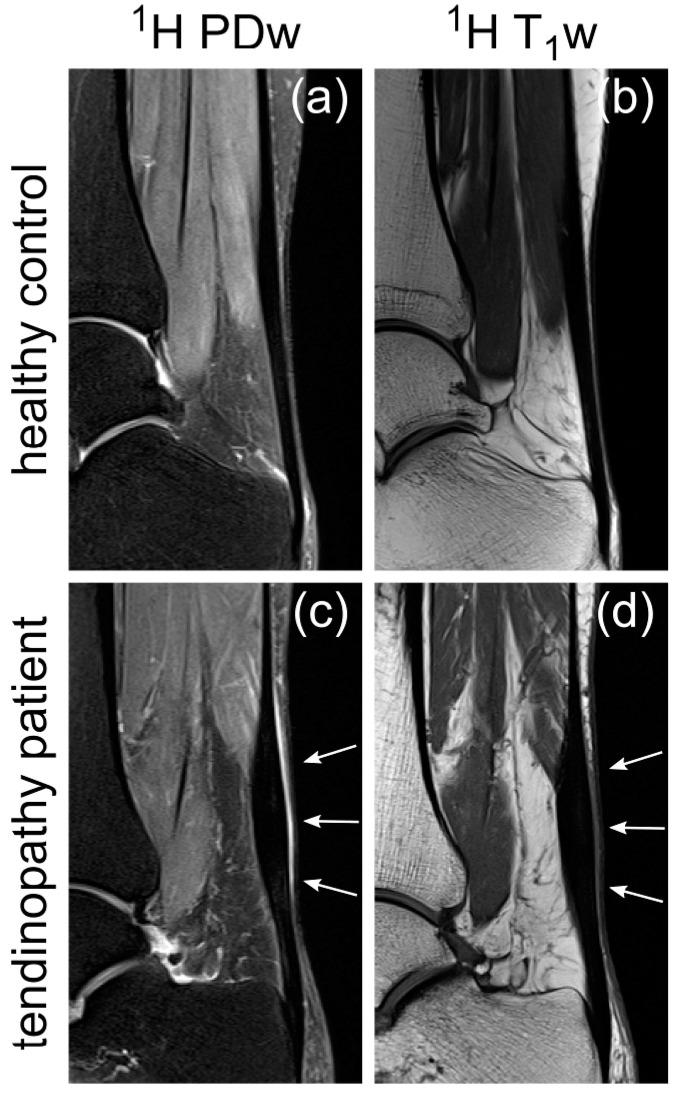

Sodium magnetic resonance imaging (MRI) can be used to evaluate the change in the proteoglycan content in Achilles tendons (ATs) of patients with different AT pathologies by measuring the Na signal-to-noise ratio (SNR). As Na SNR alone is difficult to compare between different studies, because of the high influence of hardware configurations and sequence settings on the SNR, we further set out to measure the apparent tissue sodium content (aTSC) in the AT as a better comparable parameter. Ten healthy controls and one patient with tendinopathy in the AT were examined using a clinical 3 Tesla (T) MRI scanner in conjunction with a dual tuned H/Na surface coil to measure Na SNR and aTSC in their ATs. Na T and T* of the AT were also measured for three controls to correct for different relaxation behavior. The results were as follows: Na SNR = 11.7 ± 2.2, aTSC = 82.2 ± 13.9 mM, Na T = 20.4 ± 2.4 ms, Na T* = 1.4 ± 0.4 ms, and Na T* = 13.9 ± 0.8 ms for the whole AT of healthy controls with significant regional differences. These are the first reported aTSCs and Na relaxation times for the AT using sodium MRI and may serve for future comparability in different studies regarding examinations of diseased ATs with sodium MRI.